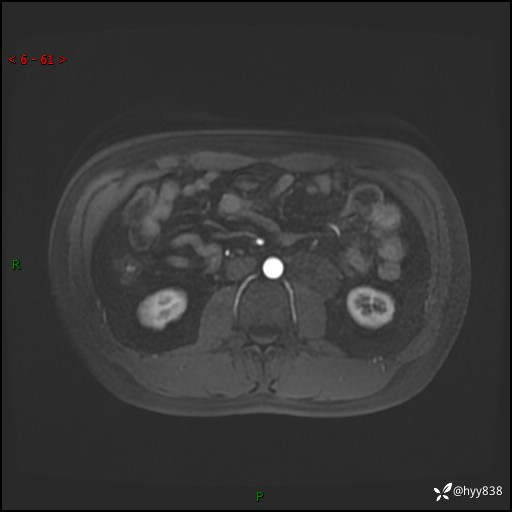

现病史:患者3月余前检查发现左侧腹膜后占位,大小约3.7*4.9cm,平素无腰疼,无肉眼血尿,无尿频尿急等不适,当时未特殊处理,在门诊复查CT提示左侧腹膜后占位,门诊拟“左侧腹膜后占位”收入院。 起病以来,患者精神佳,饮食、睡眠良好,大小便正常,体力体重无明显变化。

MRI增强